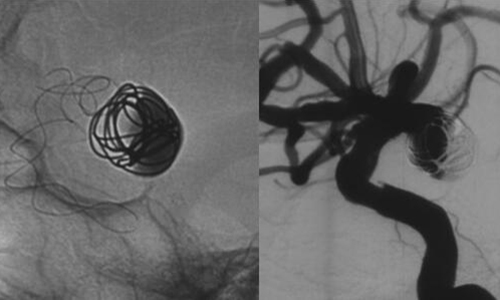

術(shù)中,張琪主任及腦血管病團(tuán)隊在劉建民教授指導(dǎo)下將Tubridge血管重建裝置專用支架導(dǎo)管T-track到位,在動脈瘤內(nèi)的一枚彈簧圈保護(hù)下,植入Tubridge5.0mm*35mm支架。準(zhǔn)確定位后,錨定支架頭端,緩慢推送支架的同時控制支架張力,順利釋放支架。為進(jìn)一步確保Tubridge血管重建裝置完美貼壁,上J型導(dǎo)絲支架內(nèi)“按摩”。多角度確認(rèn)支架已完全充分貼壁。將病變血管的腔內(nèi)重建后,正側(cè)位造影示動脈瘤內(nèi)造影劑明顯滯留,載瘤動脈通暢,血流導(dǎo)向作用顯著,分支血管均未受影響,手術(shù)取得良好效果。

▲支架完全釋放后造影,動脈瘤顯影變小,造影劑明顯滯留